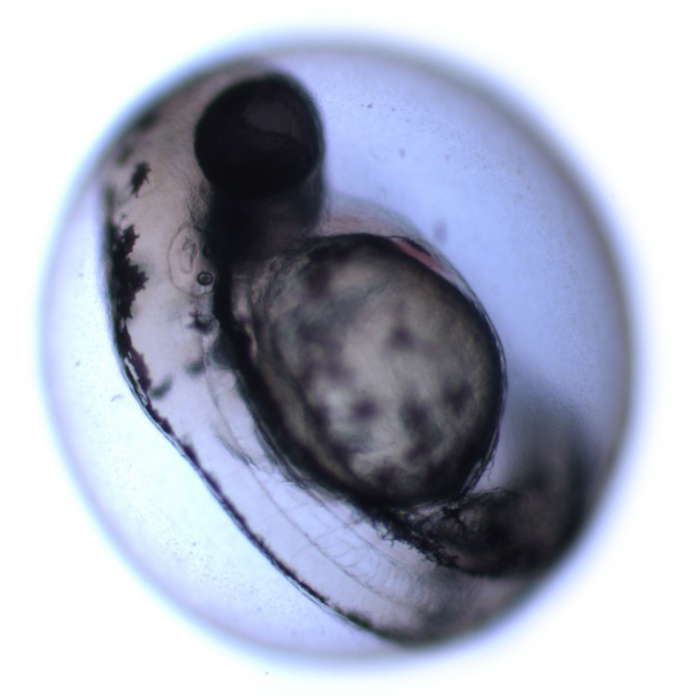

Although hair cell loss cannot be replaced in humans, many animals, including zebrafish, can restore hearing after injury through the regeneration of hair cells. The regenerative properties of zebrafish hair cells prompted researchers to use this animal to understand some fundamental properties of regeneration.

Humans and zebrafish are visually quite different, but at a genomic level, they share more than 70% of their genes. This genomic similarity offers the potential for researchers to understand the biology of cell regeneration in zebrafish before translating the findings to humans.